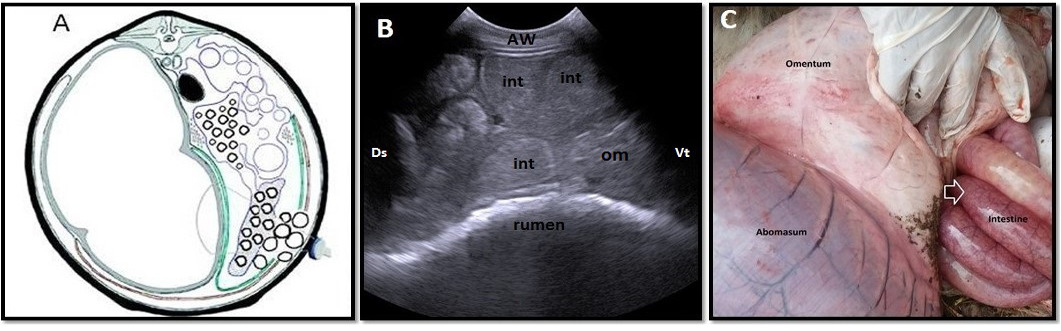

Omental herniation “entrapment” of 3-years-old-cow. A. Cross-section schematic drawing of abdomen at the level of 4th lumbar vertebra. Note intestinal entrapment through torn greater omentum. B. Ultrasonogram of ventral part of right flank region with distended intestinal loops located beneath abdominal wall with ruptured omentum (om), which located medial to intestineC. Lesions observed at necropsy. Note congestion and distension of entrapped intestinal parts through torn omentum (arrow). AW: abdominal wall; Ds: dorsal; Vt: ventral; Cr: cranial; Ca: caudal